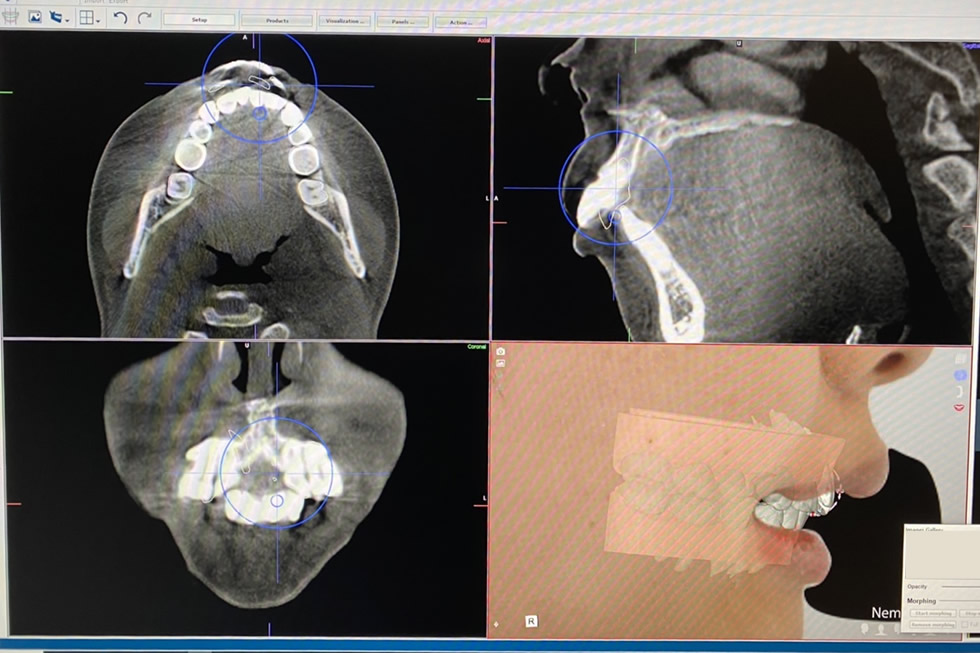

そこで、当医院では、より確実性と高い計画性を持った設計ソフト「Nemo」を導入し、より実際に近いシミュレーションを治療前に診断することができるようになりました。

口腔内スキャナーで撮影した歯型とCT画像、お顔写真など、複数のデータを照らし合わせ、科学的根拠に基づいて正確に診断し治療計画を設計することで失敗するリスクを最小限に抑えた歯列矯正が可能となりました。

顔貌スキャン:RAYFaceを導入

当医院では、3D顔貌スキャナーを導入しています。わずか0.5秒で撮影でき、自然な笑顔を撮影できます。顔貌スキャナーのデータと口腔内の3Dデータ、CTデータをインポートし、バーチャルな環境で歯列シミュレーションや診査、分析が可能です。このRAYFaceを導入することで骨格、歯列、顎関節などあらゆる角度から正確に診査・診断することが可能です。